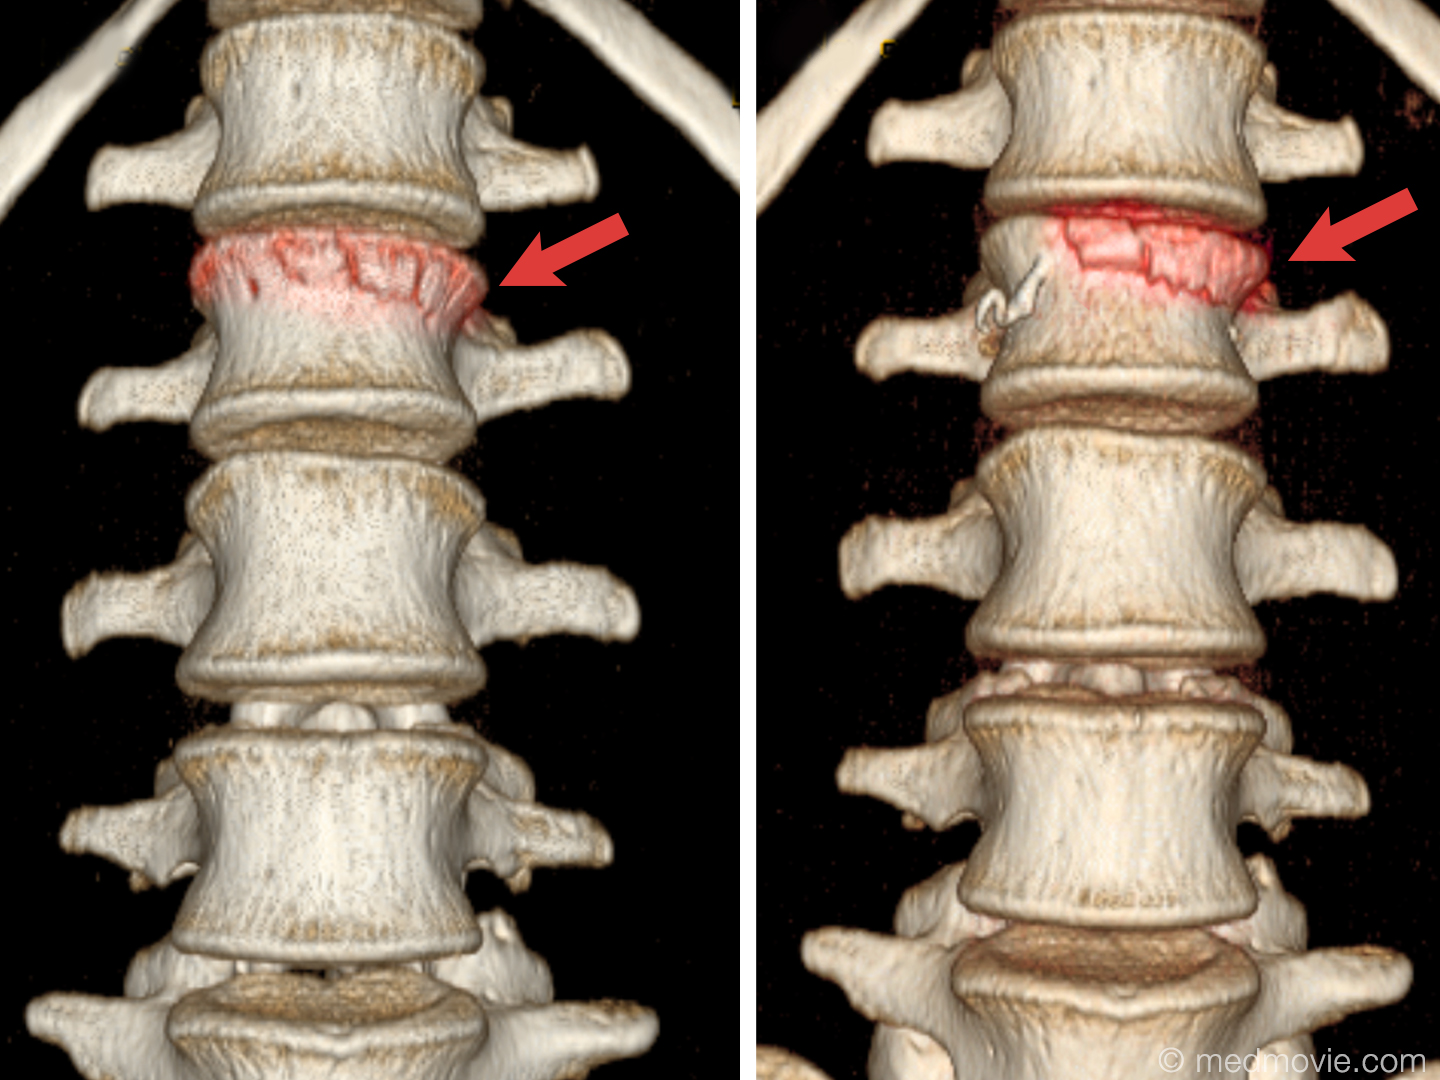

Рентгеновские снимки и медицинские изображения компрессионных переломов